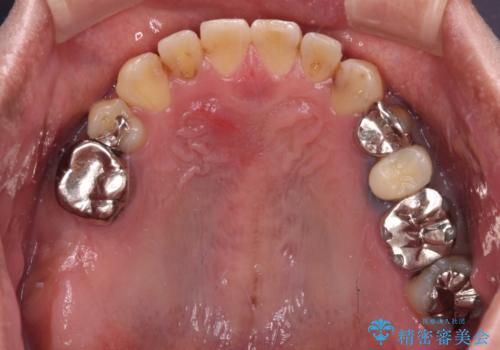

- 咬み合わせの悪さを気にして来院された患者様です。

来院当初は、奥歯の銀歯が問題で咬み合わせが悪いと思っていらっしゃいましたが、前歯の反対咬合を改善することが最優先とご説明し、矯正治療を行うこととしました。

奥歯には抜歯が必要な歯があったため、事前に抜歯を行い、その後ワイヤー装置にて治療を開始しました。